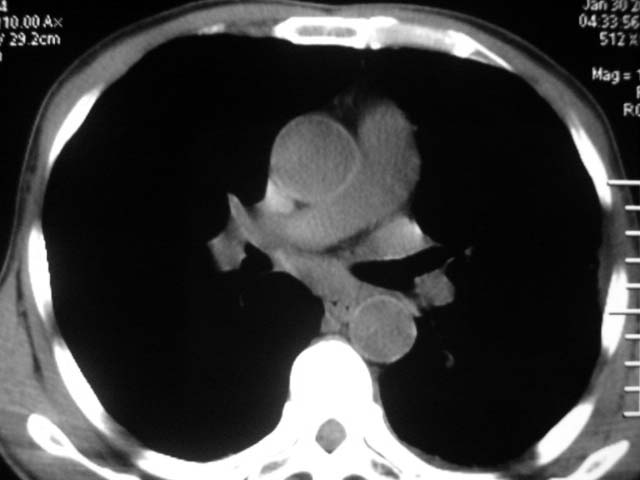

男,52岁,发热2月,糖尿病史。

抗结核治疗irpz方案,血糖未治疗,空腹15.9左右。症状无好转,左胸痛。

复查ct

2、双肺见多发片状及结节状高密度影,大多数病灶中心均见“空泡征”。

3、纵隔内淋巴结肿大。

结果:两肺继发性肺结核并曲霉菌感染。